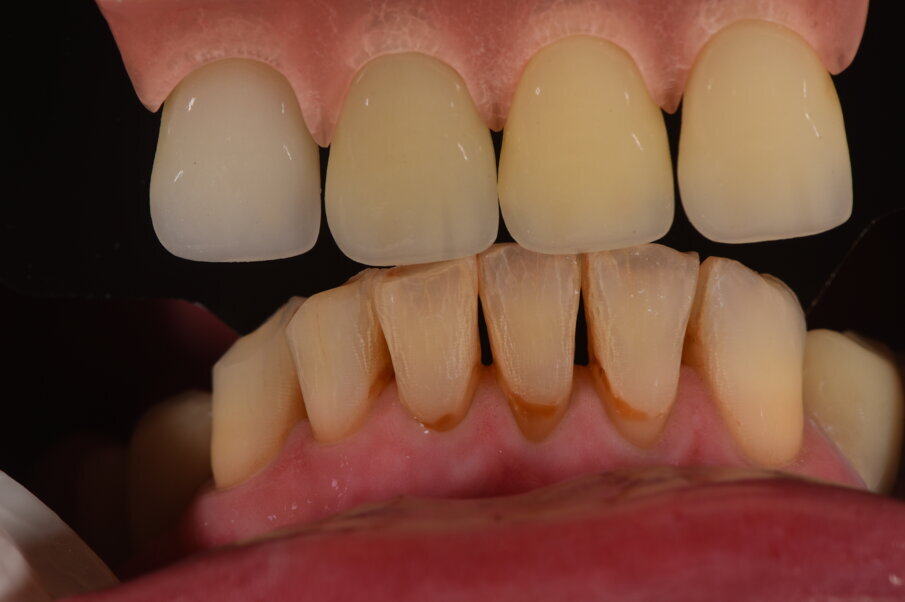

Nell’arcata inferiore dopo il trattamento parodontale abbiamo mantenuto inalterato il V° sestante provvedendo alla rimozione del 3.7 mesio-inclinato con sondaggio e mobilità difficilmente recuperabili e sostituendolo con un impianto. La scelta implantare poco convenzionale ha previsto per la sostituzione bilaterale dei diatorici con impianti in titanio di differente forma e connessione, inserendo bone level (BL) sui premolari e tissue level (TL) sui molari con una protesizzazione mista. La scelta del BL o del TL era rivolta a un aspetto estetico sui premolari e di maggior rispetto tessutale sui molari. Durante le fasi di prova (Fig. 41) si valutano le compressioni dei tragitti transmucosi (Fig. 42), gli eventuali precontatti, si finalizzano le forme e si rileva nuovamente il colore secondo la tecnica di depolarizzazione (Fig. 43).

L’appuntamento successivo sancisce l’ottimizzazione dei restauri (Figg. 44, 45). Dopo il posizionamento definitivo dei restauri protesici e l’ottimizzazione dei contatti (Fig. 46) viene nuovamente registrato l’equilibrio di masticazione tramite l’uso del sincronogiografo che registra le forze muscolari confrontando i valori registrati dal momento iniziale pre-trattamento a quello con i provvisori e infine alla stabilizzazione finale, così che nel tempo si possa aver traccia dell’adattamento realizzato (Fig. 47).